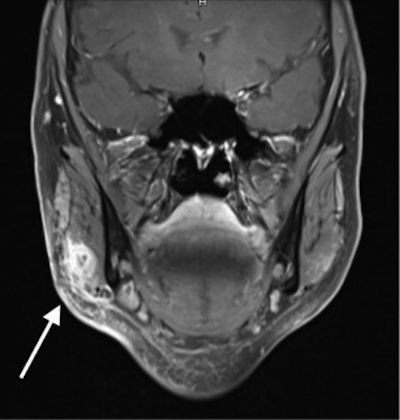

An ultrasound scan revealed an approximately 20 x 15-mm encapsulated mass. Clinicians started the patient on intravenous ampicillin/sulbactam due to the closeness of the mass to the facial nerve, and an MRI scan was performed. MRI showed a polylobulated lesion that measured 13 x 10 x 15 mm in the right masseter muscle, a facial muscle that plays a major role in chewing.

The findings were compatible with an inflammatory mass, and it was punctured and aspirated. No blood or pus emerged, which was appropriate for an accumulation of hyaluronic acid filler. Intravenous antibiotics were continued until the woman's symptoms regressed. If her symptoms had persisted with additional treatment, surgical resection would have been a final option, according to the authors.